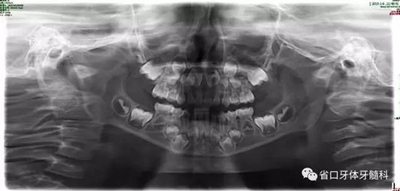

9.jpg

圖9 全景片